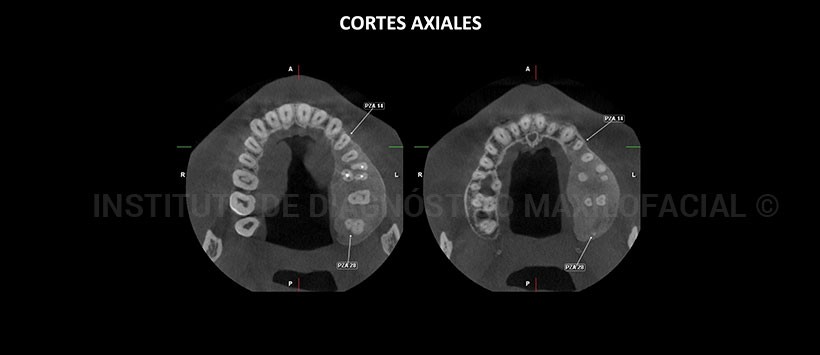

A la evaluación de la tomografía volumétrica (CBCT) cortes axiales (Figura 2), coronales (Figura 3), sagitales (Figura 4) y transaxiales (Figura 5), se aprecia aumento de volumen con alteración del patrón óseo en la región posterior del maxilar superior izquierdo que se extiende de mesial de pieza 24 hasta la región de la tuberosidad del maxilar, caracterizado por un aumento de la densidad ósea con apariencia de “vidrio esmerilado”, ocasiona expansión de las tablas óseas, de la cima del reborde alveolar y del piso del seno maxilar.